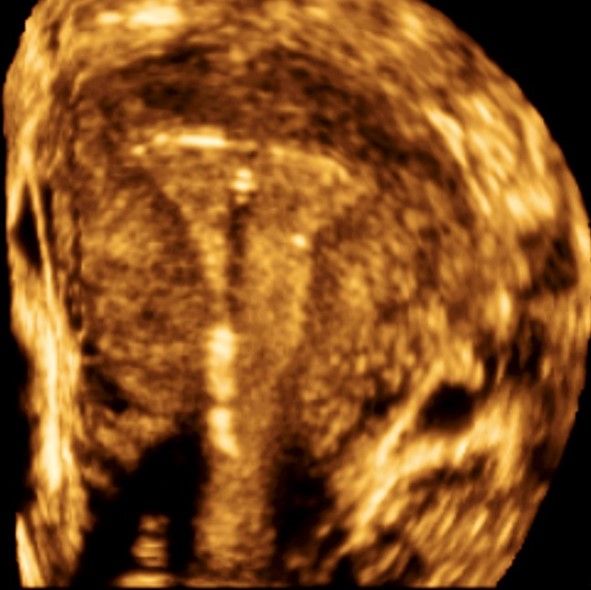

Современные экспертные УЗИ сканеры дают возможность проводить исследования всех органов в 3D. Это позволяет, используя полученный массив данных, получать диагностические сечения в любой плоскости, недоступной для обычного 2D УЗИ. Наиболее интересной является фронтальная. Например, визуализация полости матки. Диагностическая возможность выявления пороков развития превосходит все другие методы (рентгеновские и МРТ). Метод также позволяет уточнить положение ВМК (спирали) в полости матки, расположение миоматозных узлов, расположение плодного яйца на малых сроках, полипов. Сегодня современное экспертное ультразвуковое исследование невозможно без использования 3D УЗИ.